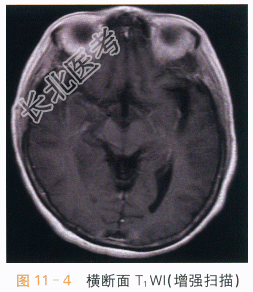

影像学资料如图11-1~图11-4所示。

读片分析:两侧岛叶及右侧颞叶可见片状异常信号影,右侧为著,呈T₁WI低信号,T₂WI、FLAIR高信号影,增强后可见轻度强化,未侵及两侧基底节区。两侧岛叶及右侧颞叶异常信号灶,右侧为著,结合患者临床表现及其它检查考虑病毒性脑炎可能。